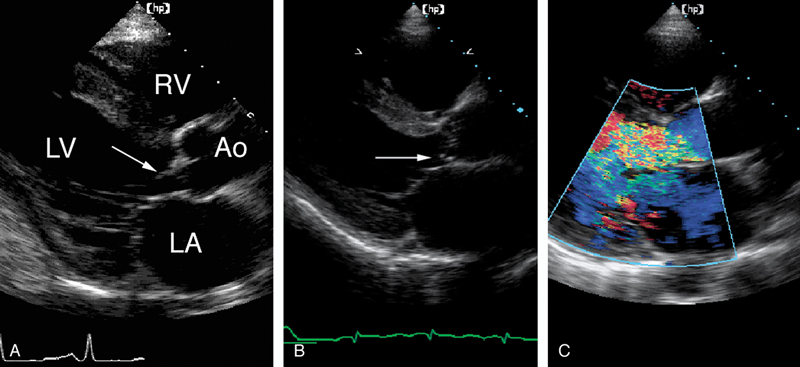

فحوصات تشخيصية لبعض امراض القلب والشرايين التاجية